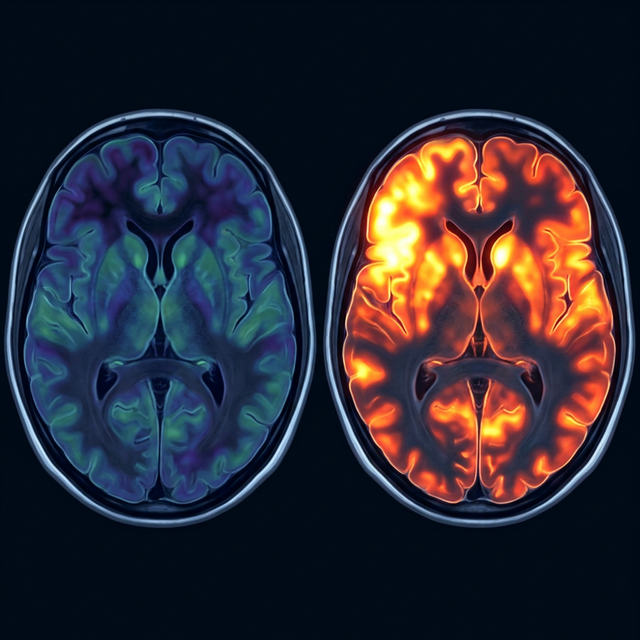

Major Depressive Disorder (MDD) is characterized by persistent a feelings of sadness, loss of interest, and a lack of energy. Research has shown that in depressed individuals, certain areas of the brain—specifically the left Dorsolateral Prefrontal Cortex (DLPFC)—are physically underactive.

This area of the brain is responsible for regulating mood, motivation, and executive function. When neural activity in the DLPFC drops, communication with deeper emotional centers (like the amygdala) becomes disrupted, leading to the entrenched symptoms of depression.

Unlike traditional antidepressants that bathe the entire brain in chemicals, TMS precisely targets this specific, underactive region to "wake it up."

Brain scan comparison showing depression